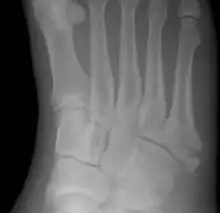

Pseudo-Jones fracture

Other proximal fifth metatarsal fractures exist, although they are not as problematic as a Jones fracture. If the fracture enters the intermetatarsal joint, it is a Jones fracture. If, however, it enters the tarsometatarsal joint, then it is likely an avulsion fracture caused by pull from the fibularis brevis tendon. An avulsion fracture at the base of the fifth metatarsal is sometimes called a "dancer's fracture" or a "pseudo Jones fracture", and usually responds readily to non-operative treatment.[18] The X-ray appearance of the developmental "apophysis" in this area may have some resemblance of a fracture, but is not a fracture; it is the secondary ossification center of the metatarsal bone. It is a normal finding that occurs at this site in adolescents.[19] If an injury to that area has occurred, the physician is often able to interpret certain radiographic clues to make the differentiation. An avulsion fracture at this location is typically extra-articular and oriented transversally as compared to the longitudinal orientation of an unfused apophysis.[19]